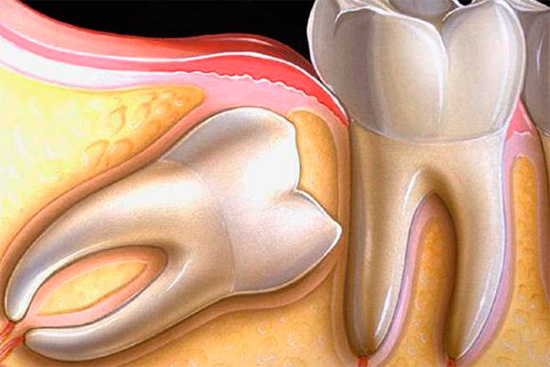

Deve-se prestar atenção especial a uma coluna na lista de preços, como a remoção de um dente retardado (não cortável) e meio dente (parcialmente aparecido). Normalmente, essa categoria reflete o problema comum que muitas pessoas enfrentam quando um dente do siso corta com apenas um ou dois tubérculos através da gengiva devido à falta de espaço ou está localizado sob a gengiva ou no osso.

Isso não traz muita preocupação para a maioria das pessoas, mas, em alguns casos, há situações clínicas em que o dente do siso repousa sobre o próximo sétimo dente, causando dor intensa à medida que o "empurra". A dor também pode ocorrer quando um dente do siso parcialmente aparecido é coberto com uma capa de gengiva, que supina constantemente e seriamente. Tudo isso e várias outras situações requerem intervenção cirúrgica imediata.

A natureza da complexidade da intervenção é determinada pelo cirurgião-dentista em uma instituição especializada e, como observado acima, a remoção nunca começa sem um raio-X. A complexidade de sua remoção depende da natureza da localização do dente no orifício. Se o dente estiver localizado completamente no osso e quase estiver ao longo da mandíbula, a operação poderá demorar muito tempo, à medida que as gengivas forem excisadas, o osso será cortado com a separação da coroa e das raízes dos dentes, seguido de uma extração em fases do orifício ósseo.